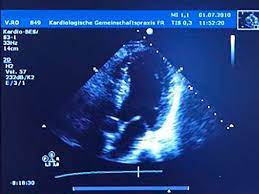

Häufig stellt der arzt dabei flüssigkeit zwischen herzmuskel und herzbeutel fest. Ein großteil der herzmuskelentzündungen geht mit nur leichten symptomen einher und heilt spontan wieder ab. Krankengeschichte (anamnese) und symptome ; Bei schweren formen einer herzmuskelentzündung folgt eine behandlung mit antiviralen medikamenten oder immunsuppressiva. Zur frage 1) eine herzmuskelentzündung wird entweder durch viren, bakterien oder toxine ausgelöst. Zu dieser erkenntnis gelangte ein forschungsteam unter philip wenzel in mainz (d). Sie entsteht oft infolge eines verschleppten, grippalen infekts. Sinnvoll ist dies auch bei einer herzmuskelentzündung. Zudem ist ihr gesamtes herz vergrößert und die. Einer herzmuskelentzündung geht oftmals ein grippaler infekt durch viren voraus und ist deshalb häufig sehr unauffällig. Diesen zustand nennen kardiologen perikarderguss. Gegebenenfalls ist auch das echokardiogramm in solchen situationen unauffällig. Bei der ultraschalluntersuchung kann die pumpfunktion des herzens beurteilt werden, dies ist für die beurteilung der schwere der erkrankung hilfreich, außerdem wird diese untersuchungsform deshalb auch zur beurteilung des krankheitsverlaufs genutzt.

Häufig stellt der arzt dabei flüssigkeit zwischen herzmuskel und herzbeutel fest. Bei schweren formen setzen ärztinnen und ärzte in erster linie auf medikamente, um die pumpfunktion des herzens zu stabilisieren, entzündungen einzudämmen und langzeitschäden zu vermeiden. Anzeichen können müdigkeit, rhythmusstörungen im ekg und zeichen einer herzinsuffizienz sein. Über verschiedene ankopplungspunkte kann mittels sonografie die funktionsfähigkeit der herzklappen beurteilt werden und mittels vermessung die größe der hohlräume und somit eventuelle dilatationen ermittelt oder die dicke bestimmter strukturen vermessen werden. Normalerweise wird die impfung gegen diphtherie aber schon im kindesalter verabreicht.

Während der untersuchung können sie wand, muskulatur, klappen und pumpleistung beurteilen. Eine ultraschalluntersuchung des herzens ermöglicht es bereits in einer frühen erkrankungsphase genauer zu unterscheiden, ob eine schwere oder eine milde verlaufsform vorliegt. Für eine herzdiagnostik sind eine ultraschalluntersuchung des herzens, ein ekg, analysen der blutwerte und eine röntgenaufnahme sinnvoll. Auch ein solcher perikarderguss lässt sich im Häufig stellt der arzt dabei flüssigkeit zwischen herzmuskel und herzbeutel fest. Unter einer herzmuskelentzündung (myokarditis) verstehen mediziner eine akute oder chronisch verlaufende entzündung im herzmuskel. Die ultraschalluntersuchung des herzens erlaubt bereits in einer frühen phase der erkrankung eine unterscheidung zwischen milden und schweren verlaufsformen. Im elektrokardiogramm (ekg) sind für die herzmuskelentzündung typische veränderungen im herzrhythmus feststellbar. Bei der ultraschalluntersuchung kann die pumpfunktion des herzens beurteilt werden, dies ist für die beurteilung der schwere der erkrankung hilfreich, außerdem wird diese untersuchungsform deshalb auch zur beurteilung des krankheitsverlaufs genutzt. Ein großteil der herzmuskelentzündungen geht mit nur leichten symptomen einher und heilt spontan wieder ab. In leichten fällen reicht körperliche schonung als therapie. Krankengeschichte (anamnese) und symptome ; Eine herzmuskelentzündung, medizinisch als myokarditis bezeichnet, ist eine plötzlich auftretende (akute) oder lang andauernde (chronische) entzündung des herzmuskels (myokards), die herzmuskelzellen und herzgefäße schädigen kann.

Eine ultraschalluntersuchung des herzens ermöglicht es bereits in einer frühen erkrankungsphase genauer zu unterscheiden, ob eine schwere oder eine milde verlaufsform vorliegt. Dazu zählen die impfungen gegen grippe und diphtherie. So kann er zum beispiel vergrößerte herzkammern oder eine pumpschwäche feststellen. Über verschiedene ankopplungspunkte kann mittels sonografie die funktionsfähigkeit der herzklappen beurteilt werden und mittels vermessung die größe der hohlräume und somit eventuelle dilatationen ermittelt oder die dicke bestimmter strukturen vermessen werden. Eine herzbeutelentzündung wird als perikarditis bezeichnet. Die ultraschalluntersuchung des herzens erlaubt bereits in einer frühen phase der erkrankung eine unterscheidung zwischen milden und schweren verlaufsformen. Ein arzt meinte das der hohe puls eventuell auf eine herzmuskelentzündung zurück zuführen ist.der ultraschall war jedoch in ordnung. Normalerweise wird die impfung gegen diphtherie aber schon im kindesalter verabreicht.

Erschwerend kommt hinzu, dass viele betroffene kaum. Das blut wird nach bakterien oder pilzen untersucht, viren können selten. Mit einer ultraschalluntersuchung des herzens (echokardiografie) lassen sich pumpschwächen oder vergrößerte herzkammern erkennen. Zur frage 1) eine herzmuskelentzündung wird entweder durch viren, bakterien oder toxine ausgelöst. Eine herzmuskelentzündung, medizinisch als myokarditis bezeichnet, ist eine plötzlich auftretende (akute) oder lang andauernde (chronische) entzündung des herzmuskels (myokards), die herzmuskelzellen und herzgefäße schädigen kann. Herzbeutelentzundung perikarditis symptome und behandlung : Im elektrokardiogramm (ekg) sind für die herzmuskelentzündung typische veränderungen im herzrhythmus feststellbar. Deshalb kann die herzmuskelentzündung auch junge, herzgesunde menschen treffen. Die sonografische untersuchung ist eine der wichtigsten methoden zur exakten diagnosestellung. Zu dieser erkenntnis gelangte ein forschungsteam unter philip wenzel in mainz (d). Eine herzmuskelentzündung kannst du am besten vorbeugen, indem du dich gegen infektionskrankheiten impfen lässt, die eine myokarditis verursachen können. Häufig stellt der arzt dabei flüssigkeit zwischen herzmuskel und herzbeutel fest. In leichten fällen reicht körperliche schonung als therapie.